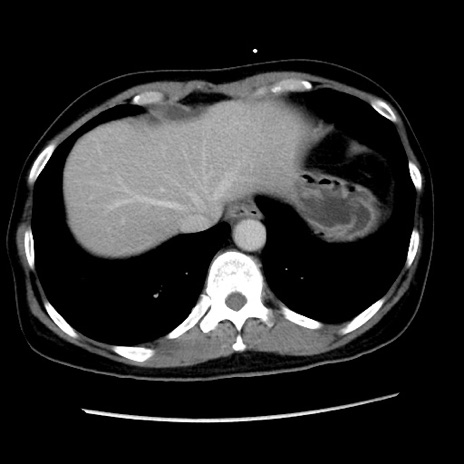

冠状断像

【症例】 50歳代女性

【主訴】 腹痛

【現病歴】前日生レバーを食べた。今朝に排便あり。 昼前に突然発症の腹痛を生じ、当院救急外来を受診した。

【身体所見】 意識清明、腹部:平坦、軟、下腹部やや左を中心に圧痛・反跳痛あり、筋性防御あり